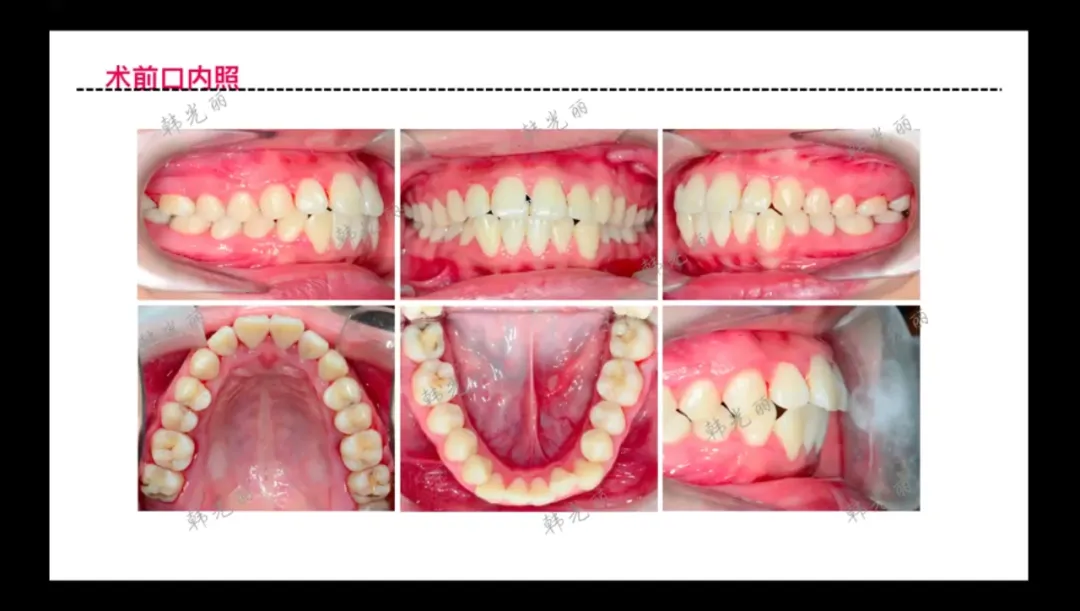

中间下面这张口内正面图覆合较深,前牙内倾,后牙向缺隙中伸长的。

: 前牙内倾、后牙伸长倾倒的"过山车效应"

女孩双颌前凸案例

• 口腔情况

:牙列整齐但存在双颌前凸,兼具牙性与骨性前突特征